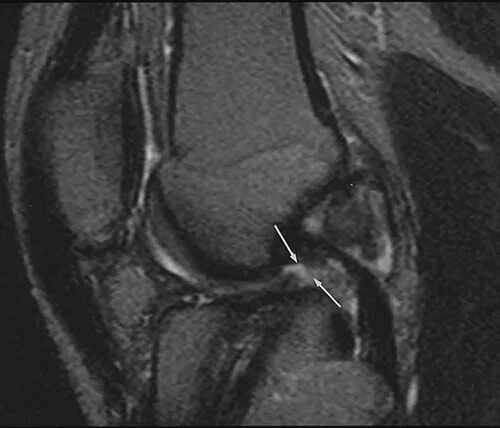

Мрт суставов пермь